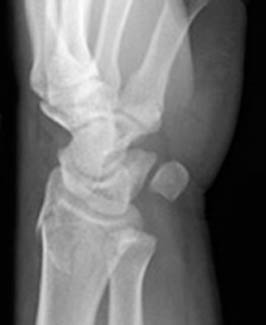

8) Name the abnormality shown in the image below.

9) When evaluating the fracture shown in the question above, what secondary fracture should also be looked for?